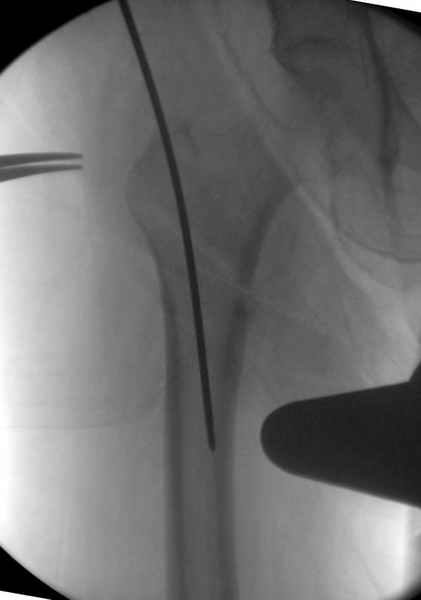

Здесь сканнированные снимки импланта и операционные снимки больной.